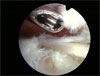

Tu zerwanie widoczne z regionu podbarkowego ze sciegnem miesnia dwuglowego ( po prawej stronie)

Zerwanie widziane podczas artroskopii ( małe i duże).